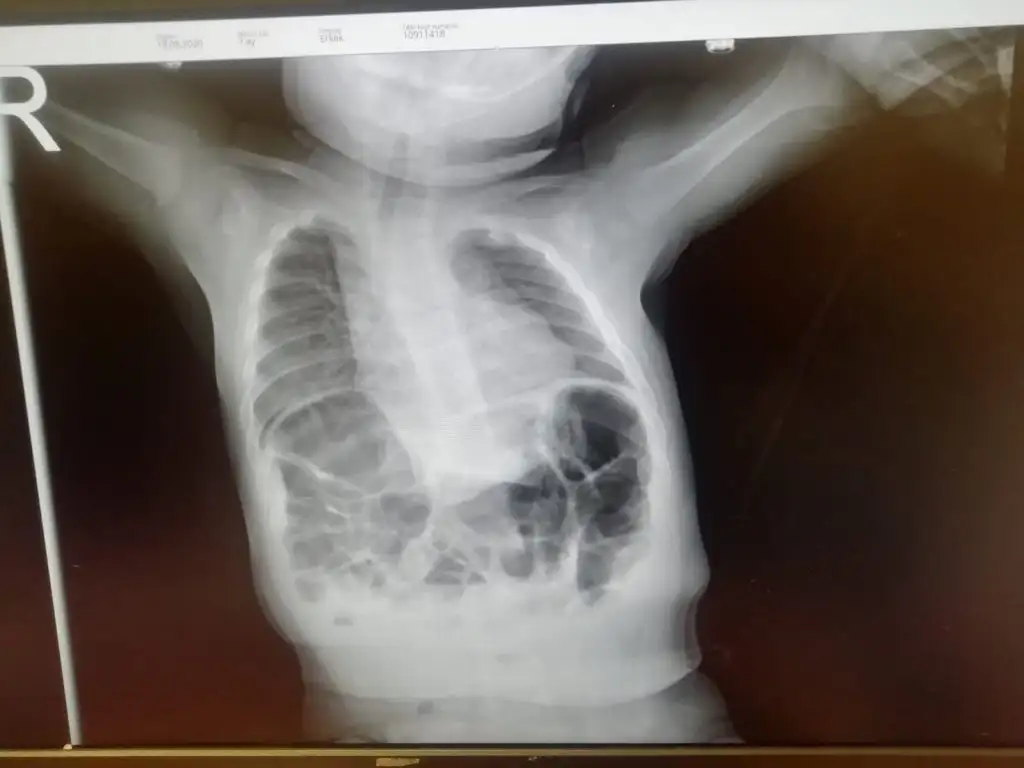

bunu söyledi ilk canım,konuya da bir arkadaş etiketlemişti beni zaten,sonradan dahil oldum. S sassyassyyCok karmasik bir konu yani doktorlar tam tespit edemedi bazikari nefes borusu ile soluk borus yapisik onun icinde agir bir ameliyat olmasi gerekiyor dedi bazilari bagursagi yukarda kalbi buyuk dedi ve sol cigerinde sorun varmis ve zaten bronsit en son doktor bir uzmana goturun cocugun durumu kotuye gidiyor nefes alamiyor dedi

konu sahibi önce bir çocuk doktoruna gidin. birkaç görüntüleme yapılsın,bahsettiğiniz şeyler bana farklı farklı şeyleri düşündürdü,yani hepsinin bir arada olması.. sendromik bir şey de olabilir. görüntüleme sonuçlarını özelden atabilirsiniz bana, bağırsakları göğüs kafesine mi fıtıklaşmış mesela? eğer öyleyse akciğerinin bir tarafını ezip sönmesine sebep olmuş olabilir tabi,e bu durumdan kalp de etkilenir doğal olarak, yani tabi bu benim sizin şu yazdıklarınızdan anladıklarıma göre yaptığım tahminler sadece ,kesin olarak organlar nerede ne durumda bir görmemiz lazım.

doğrudan cerraha götürmeyin, çocuk doktoru muayene etsin,gerekirse yeşil alan açıp sizi cerraha yönlendirirler zaten.

en son bu grafinin çok nonspesifik olduğunu,mutlaka ileri görüntülemenin gerektiğini söyledim.Çocuk kaç yaşındaydı?

şimdi Cansu hanım bu filme bakarak net bir şey söyleyemem ancak çocuğun sağına bakarsanız bağırsakların orada olmaması lazım yani karaciğer seçilemiyor maalesef, buna bağlı olarak diyaframa barsak fıtıklaşmış ve oradaki akciğer alanını söndürmüş olabilir. ( yine dikkatli bakarsanız soluk borusu da sağa itilmiş zaten orta hatta olması gerekirken) Buna atelektazi diyoruz, buna bağlı olarak da sık enfeksiyon ve nefes darlığı görülebilir.

bana kalbi büyük gelmedi, timus bezinden dolayı öyle gözüküyor olabilir. Ancak dediğim gibi bu grafide hiçbir şey net değil, tomografi ve ultrasonunu görmem lazım mutlaka.

siz ilk iş çocuk doktoruna randevu alın, ultrason ve tomografi ister onlar, sonra sizi cerrahiye yönlendirirler.

bu aşamada nesi var söylemem mümkün değil maalesef

E yani? Bilmediğimden çok bişey anlamadım, dedikleri ile tutmuyor mu bu röntgen şimdi?bunu söyledi ilk canım,konuya da bir arkadaş etiketlemişti beni zaten,sonradan dahil oldum. S sassyassyy

film istedim,bana bunu yolladı.

yok soluk borusuyla yemek borusu yapışık,yok tek akciğeri yok,kalbi büyükmüş,durumu acil hemen yatırılması tedavi edilmesi gerekli demişti.

birbiriyle alakasız birçok semptomdan bahsedince acaba sendromik bir şey mi dedim benim bilmediğim, ama madem ciddi solunum sıkıntısı var bakın kaç hafta önce konuşmuşuz,haftalardır naptı bu çocuk?

solunum sıkıntısı olan çocuk taburcu edilmez,yatırılması lazım,cansu hanımın dediğine göre her doktor bir şey söylemiş,anlamadım kafam da karışmadı değil hani.

en son bu grafinin çok nonspesifik olduğunu,mutlaka ileri görüntülemenin gerektiğini söyledim.

bir anormallik var grafide ama,kendi çocuğunun mu bilmiyorum açıkçası. (alıntıyı ekledim,anormallikleri yazdım.)